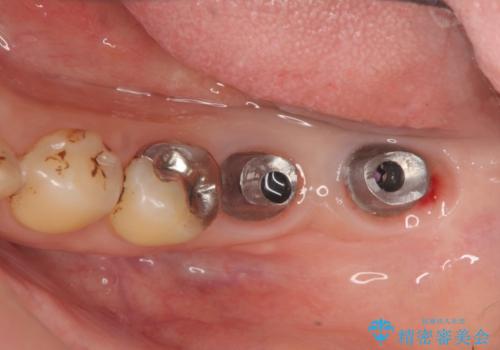

歯周病に対する全体治療

再生治療、歯周外科を行うことで歯周病治療を行い、残すことのできる歯の歯周環境を整える。

残すことのできない歯は抜去したのち骨造成を含めたインプラント治療を行い、しっかりとした咬合関係を確立していきます。

治療期間はかかりましたが、しっかりと歯周病治療・インプラント治療を行ったおかげで歯周病の状態は非常に良くなり、安定した咬合関係を確立することができました。